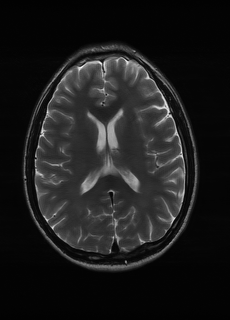

Base on the best performing {λs}s=1Ssubscriptsuperscriptsubscript𝜆𝑠𝑆𝑠1\{\lambda_{s}\}^{S}_{s=1}, we perceive that among T1subscript𝑇1T_{1}, T2subscript𝑇2T_{2}, and FLAIR, the results are best when T2subscript𝑇2T_{2} is sampled the most. We suggest that this makes intuitive sense as T2subscript𝑇2T_{2} images provide the best contrast out of the three sequences, which can compensate for the details lost in other images. The same observation can be made on the simulated data, where both T2subscript𝑇2T_{2} and FLAIR show good contrast. When the time setting is changed to non-uniformity, we can see that our search for the best sampling strategy reflects the change. T1subscript𝑇1T_{1} is sampled more as a result of faster acquisition time, while T2subscript𝑇2T_{2} is still sufficiently sampled.